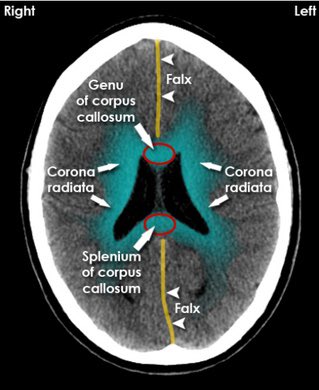

▫️الحرف الرابع "V”

⏺ويقصد فيه ال Ventricle

✳️لازم نستبعد وجود دم في الحجرات زي اللي يحدث في حالات ⬅️ Interventricular hemorrhage

أو وجود أستسقاء مثل Hydrocephalus

✳️ ولازم نركز على حجم حجرات الدماغ ونتأكد أنها متساوية